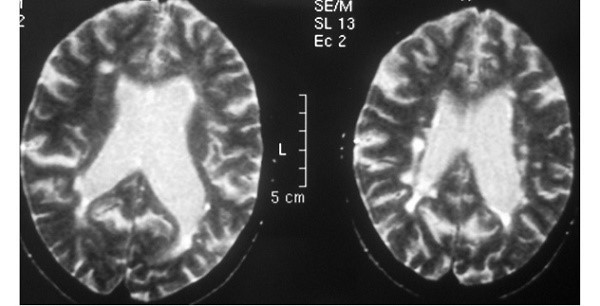

Перивентрикулярная лейкоэнцефалопатия, известная как перивентрикулярная лейкомаляция, характеризуется возникновением очагов поражения белого вещества чаще возле желудочковой системы. При масштабном поражении очаги распространяются в центральные отделы белого вещества.

Демиелинизирующий процесс агрессивного, длительного течения приводит к образованию некротических полостей в мозговых структурах. Лейкоэнцефалопатия (лейкомаляция) головного мозга, обнаруженная у детей, часто является причиной развития в детском возрасте церебрального паралича (ДЦП).

Исследование КТ показывает двухсторонний лейкоареоз – малую ишемию сосудов, повреждения элементов сосудистой системы белого вещества. При перивентрикулярной лейкоэнцефалопатии на МР-томограмме различается диффузно-очаговое поражение белого вещества преимущественно симметричное.

Лейкопатию головного мозга у ребенка вызывает гипоксия, возникшая при родах. Инструментальные методы диагностики позволяют увидеть участки гибели ткани, преимущественно рядом с мозговыми желудочками.

Перивентрикулярные волокна несут ответственность за двигательную активность, и их поражение ведет к детскому церебральному параличу. Очаги поражения возникают симметрично, в особо тяжелых случаях обнаруживаются во всех центральных зонах мозга.

Мелкоочаговая и перивентрикулярная лейкоэнцефалопатия

Современное название патологии – перивентрикулярная лейкомаляция. Заболевание сопровождается образованием очагов омертвелой ткани в белом веществе мозга. Встречается у детей и является одной из причин детского церебрального паралича. Лейкоэнцефалопатия головного мозга у детей встречается обычно у мертворожденных.

Лейкомаляция, или размягчение белого вещества, возникает вследствие гипоксии и ишемии головного мозга.

Обычно ассоциируется с пониженным артериальным давлением у ребенка, нарушением дыхания сразу после родов или осложнениями в виде инфекции.

Перивентрикулярная лейкоэнцефалопатия головного мозга у ребенка может развиться вследствие недоношенности или вредных привычек матери, из-за чего у ребенка в период внутриутробного развития была интоксикация.

У мертвого ребенка может встречается комбинированный вариант – многоочаговая и перивентрикулярная лейкоэнцефалопатия сосудистого генеза. Это сочетание сосудистых нарушений, например, врожденных пороков сердца и нарушения дыхания после рождения.